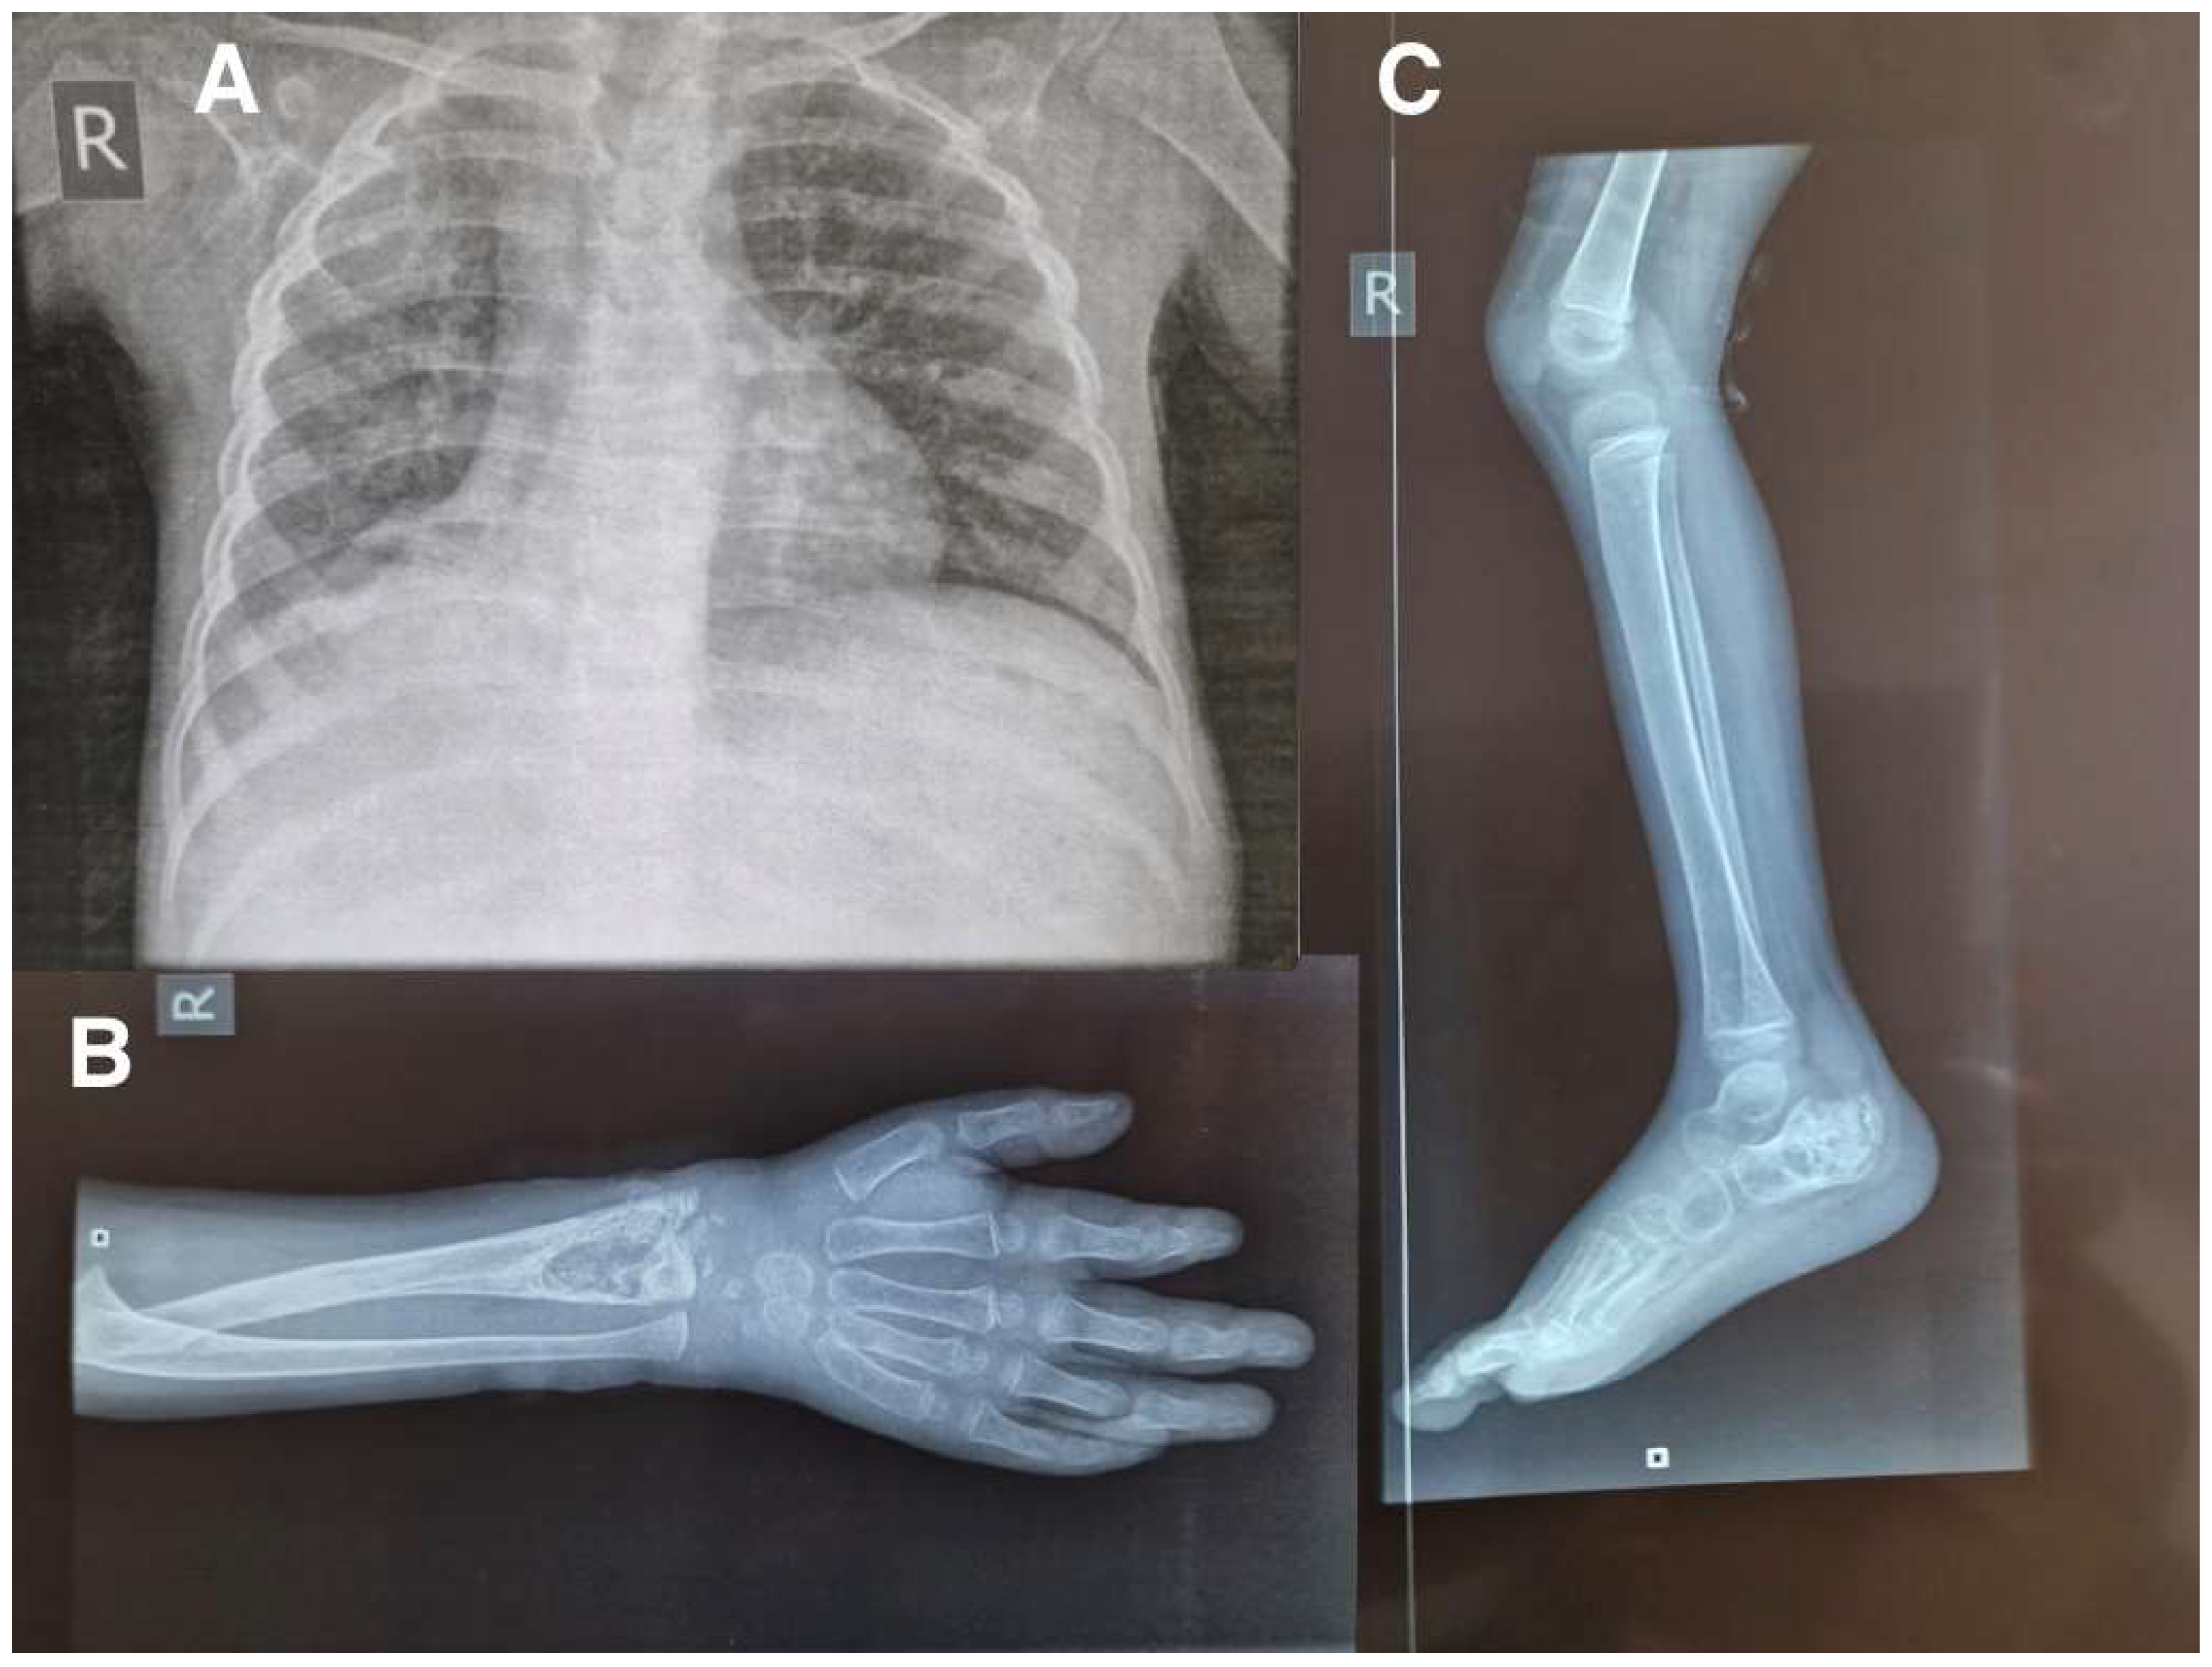

2. Case Report